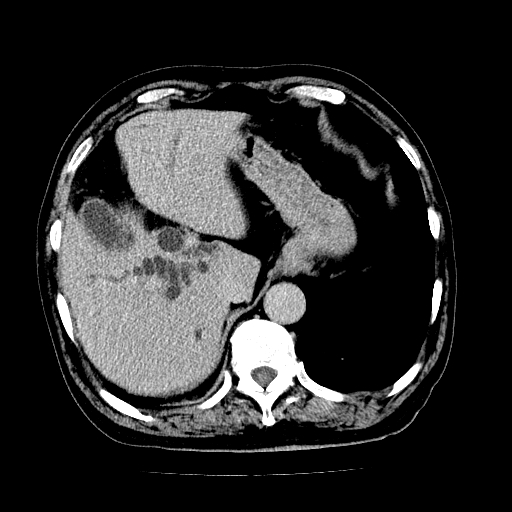

男,71岁,皮肤黄染四天。

肝内外胆管及胆总管上段扩张,考虑为梗阻所致,建议mrcp检查。

考虑胆总管癌并肝内外胆管扩张。

胰腺上端胆总管内见软组织影,强化不明显,结合临床,还是考虑低位梗阻性黄疸,胆总管癌可能性大